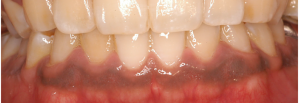

メラニン色素沈着の除去

マイクロスコープとEr:YAGレーザーの併用で、術後の痛みもほとんどありません。